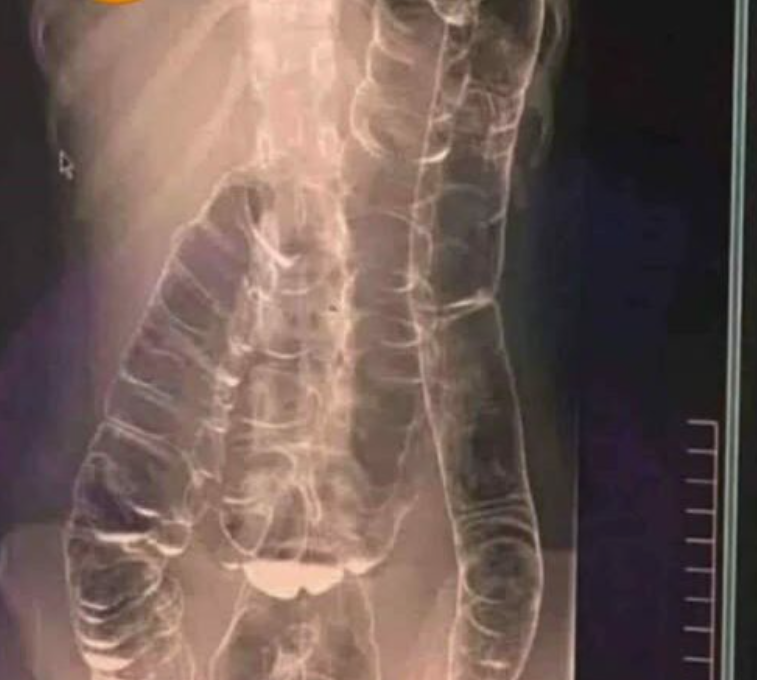

The human digestive system is a marvel of biological engineering — a complex processing line that extracts vital nutrients and eliminates metabolic waste. When it functions properly, it remains almost invisible in the background of a healthy life. But when the elimination process is disrupted, chronic constipation can develop. Far from being just a minor discomfort or social inconvenience, chronic constipation is considered by health professionals to be a “silent enemy” of digestive well-being. If left untreated, it can trigger a chain of problems — from hemorrhoids and anal fissures to more serious complications such as fecal impaction or disruption of the gut microbiome. Understanding how this condition works and the lifestyle changes needed to correct it is essential for long-term health.

The primary role of the large intestine is to absorb water from food waste and form stool. Constipation occurs when the muscular contractions of the colon are slow, causing waste to move too slowly through the digestive tract. The longer stool remains in the colon, the more water is absorbed, making it hard and difficult to pass. Over time, this creates an unhealthy internal environment. The body may begin to reabsorb substances that were meant to be eliminated, leading to symptoms beyond the digestive system: brain fog, skin issues, persistent fatigue, and a general feeling of heaviness.

If constipation persists despite dietary and hydration changes, or is accompanied by warning symptoms such as severe bloating, persistent vomiting, or blood in the stool, medical attention is necessary. These signs may indicate bowel obstruction or a serious inflammatory condition. Ignoring them can result in dangerous complications such as intestinal perforation or sepsis.